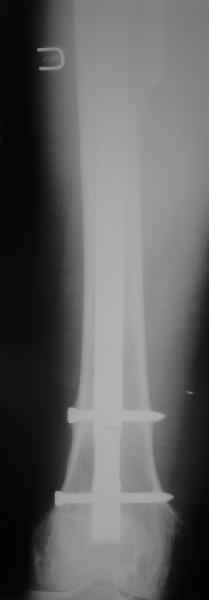

Хотел бы обратить Ваше внимание, что реакция кортикала наблюдается только вокруг проксимального винта, дистальный винт не испытывает подобной нагрузки. Отсюда еще одна умозрительная авантюра - выкрутить только проксимальный винт. Изменения кости вокруг дистального винта тоже могут дать ответ на счет интеграции ножки, также как и появляется возможность сломать его. Страховаться (затратнее, но надежнее) или нет(легче, но не безопасно) динамическим винтом - на Ваш выбор.

Другой вариант перенести нагрузку на кость, "боем" проверив фиксацию ножки. Динамически заперев винт на 5мм ниже проксимального края овального отверстия. Статические винты отпереть, пациенту рекомендовать постепенно возрастающую дозированную нагрузку до полной в течение месяца. Хотя срок интеграции бесцементника считается 3 месяца(так пишут в руководствах и рекомендациях), если допустить, что ножка не интегрировалась. Появление клиники или проседание ножки по рентгенограмме даст ответ на счет того произошла ли интеграция или нет. С другой стороны проседание на 5 мм вряд ли приведет к чему либо серьезному, и если интеграции нет - рассматривать вопрос о ревизии. Если ножка интегрировалась, стрежень не удалять - для избежания перипротезных переломов.

Вот если мы в динамике увидим намек на это, тут-то точно надо будет удалить винты.